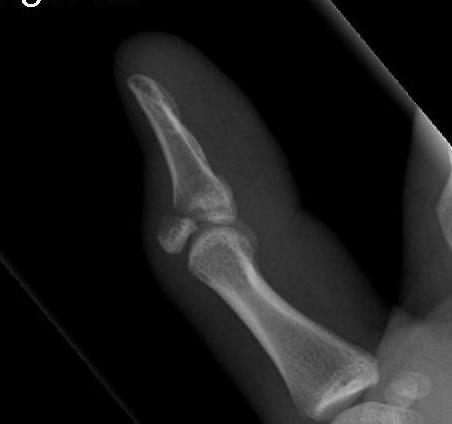

2. Bony fracture

Drop finger / extension lag of the DIPJ

Axial load

- extensor tendon attached to bony fragment

- volar subluxation of distal phalanx

- fragment > 50% joint surface